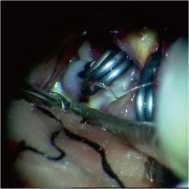

弹簧圈栓塞后造影示左椎动脉夹层动脉瘤消失, 左椎动脉、 多发动脉瘤夹闭术前、术中

左侧小脑后下动脉循环通畅

动脉瘤开颅夹闭术示意图